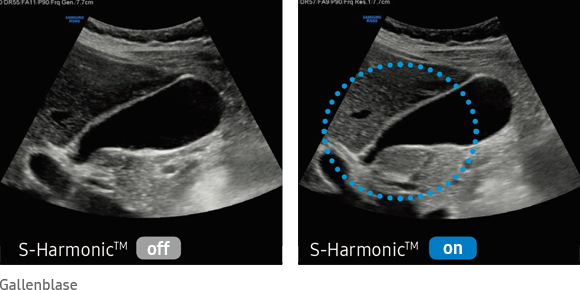

S-Harmonic™

The new S-Harmonic™ technology enables brilliant images both near the surface and in depth. It minimizes noise and thus ensures homogeneous ultrasound images.